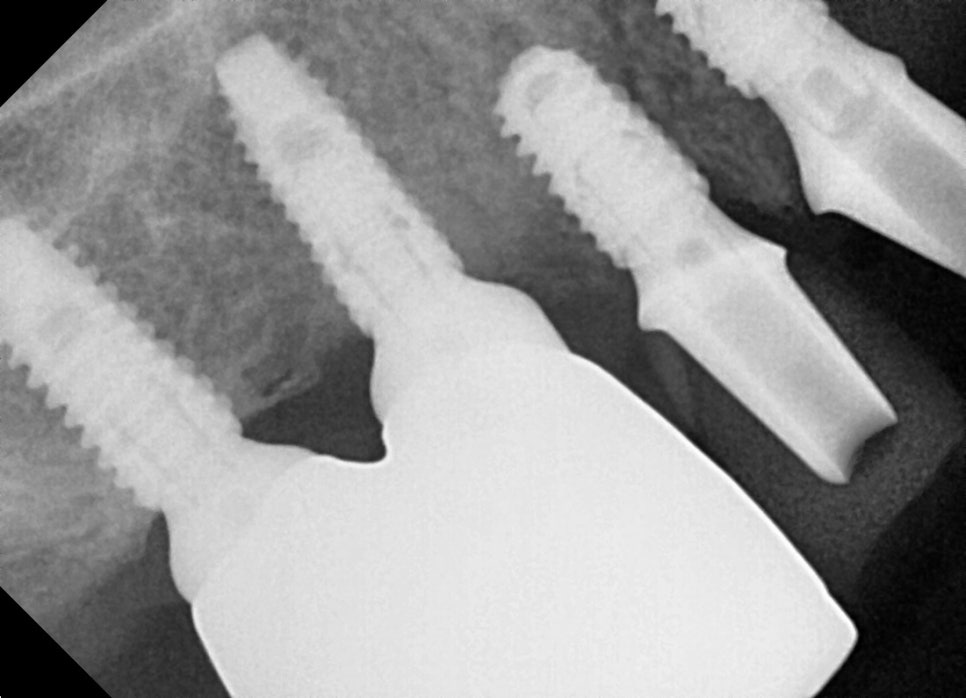

Extraction + implant placement, performed at the same time

Seoulove Dental Hospital implant treatment

After extracting the old prostheses and weakened teeth,

we placed implants immediately in the necessary areas.

Areas lacking sufficient bone were supplemented with GBR to ensure stable support.

The angles of the upper and lower jaw implants were precisely placed in the preplanned positions based on CT data.